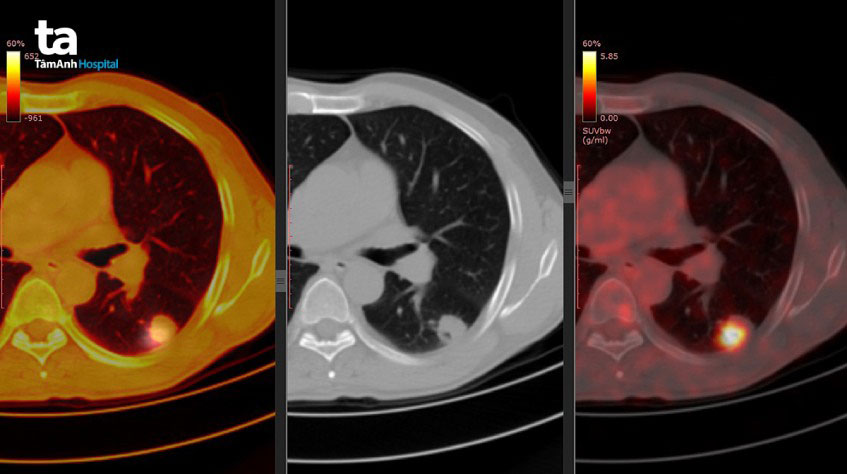

Phương pháp này có thể được áp dụng để đánh giá mức độ lan rộng của ung thư và xác định liệu ung thư có di căn hay không.

Các kỹ thuật này giúp tạo hình ảnh chi tiết của vùng bị nghi ngờ, giúp phát hiện ung thư hoặc tình trạng di căn.

Đây là phương pháp quan sát toàn bộ cơ thể để phát hiện sự hiện diện của ung thư và xác định các vùng di căn mà chưa được xác định rõ qua các xét nghiệm khác. Các xét nghiệm trên đóng vai trò quan trọng trong việc xác định mức độ xâm lấn và di căn của ung thư, từ đó giúp xây dựng kế hoạch điều trị phù hợp.